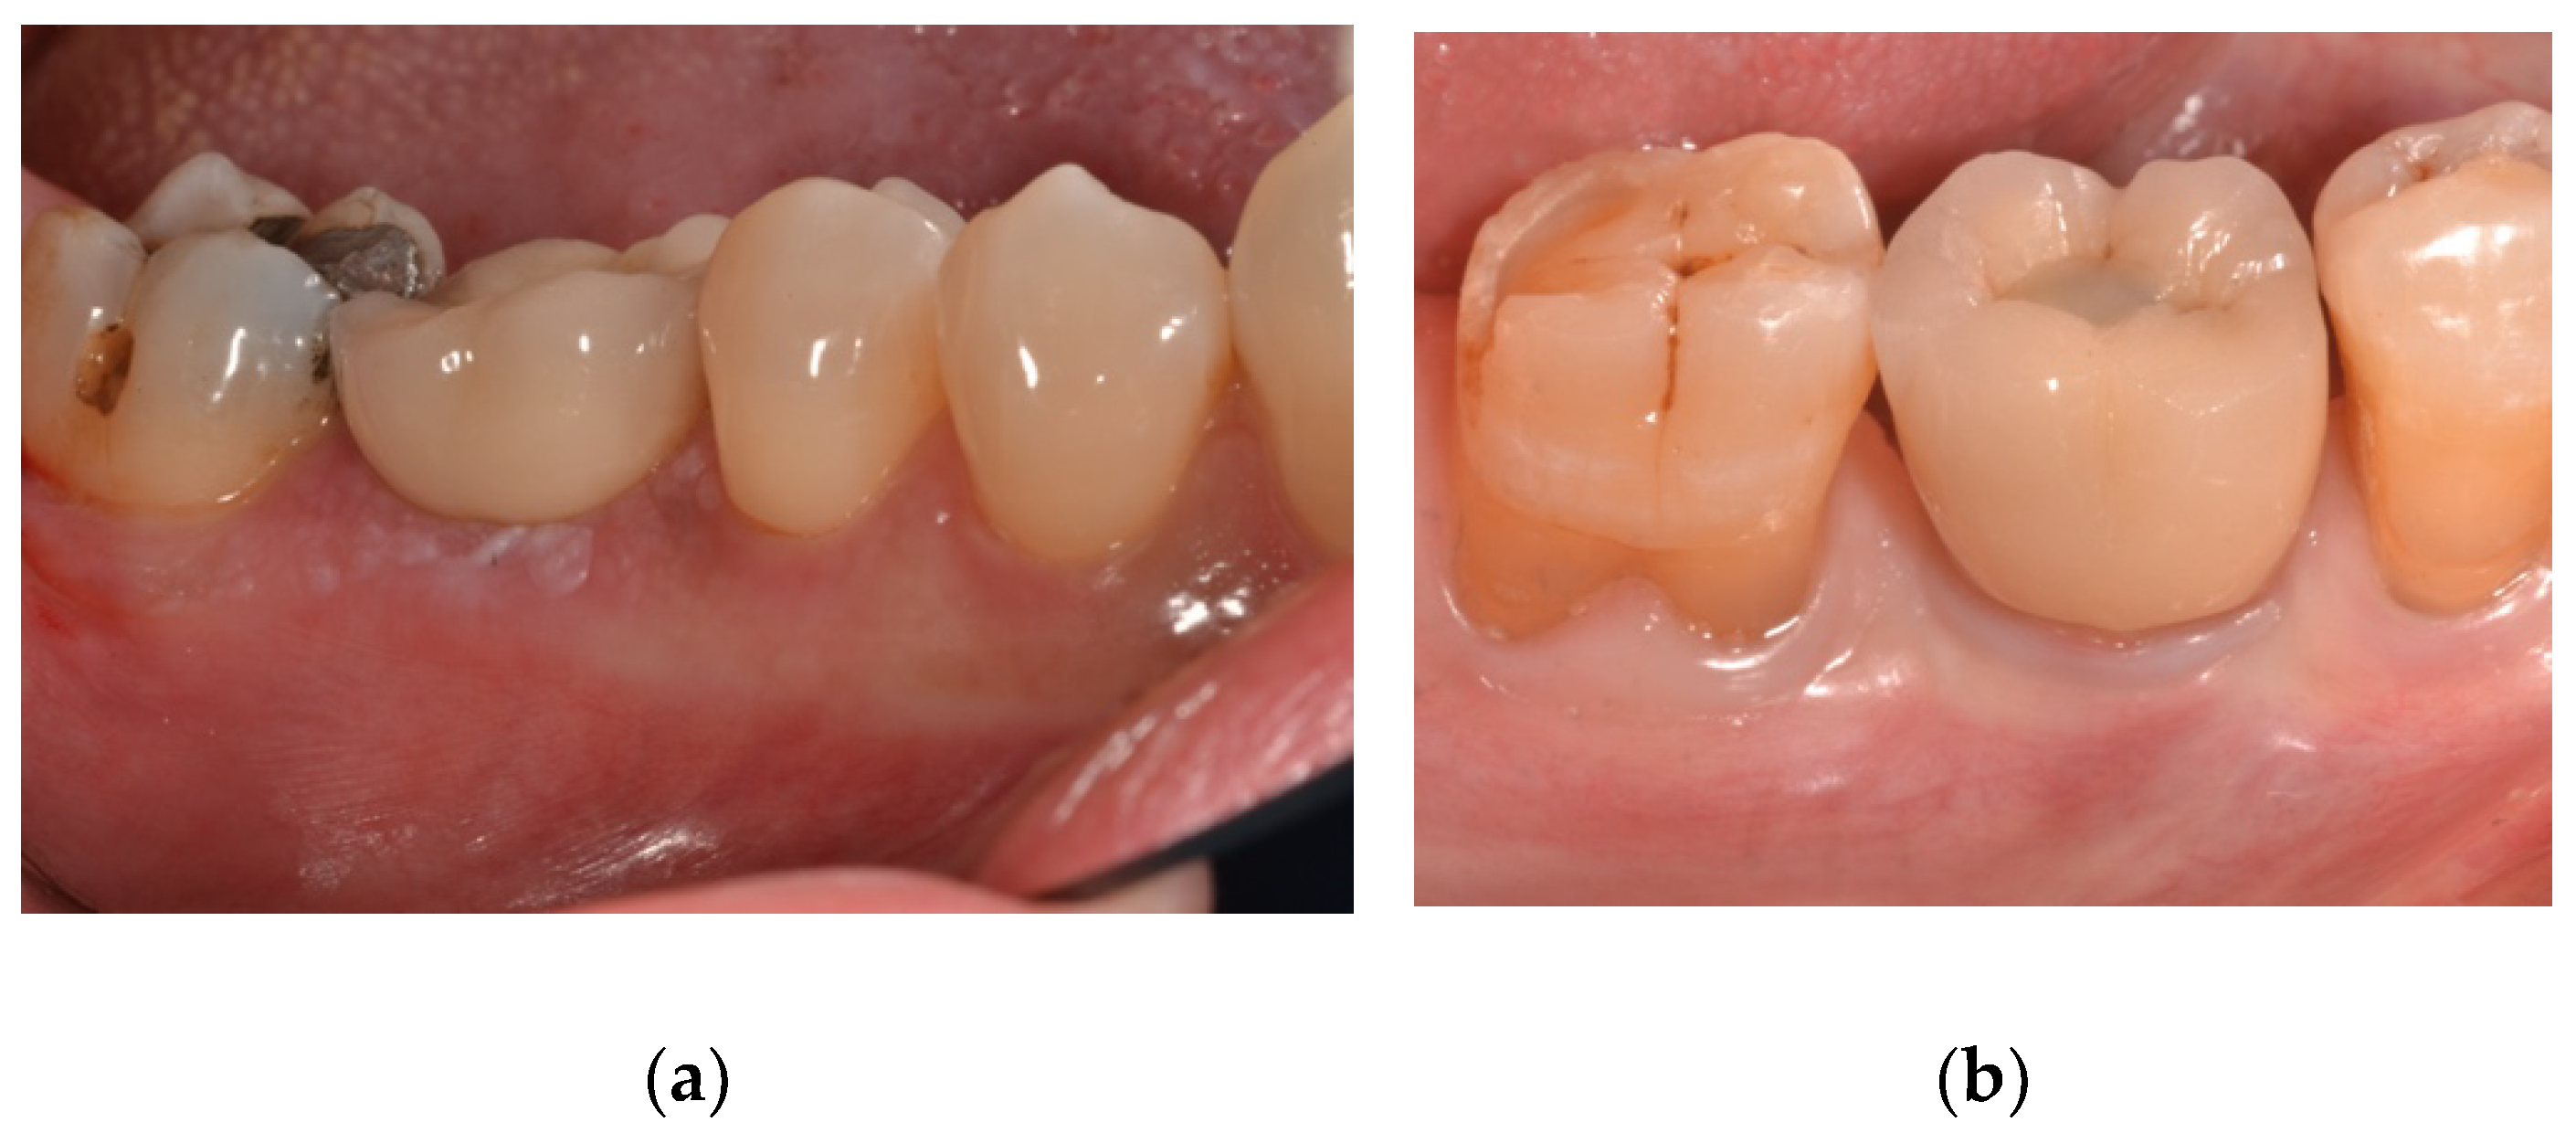

| PES | The aesthetic evaluation was performed according to the pink esthetic score (PES) on the vestibular and occlusal pictures taken including at least one adjacent tooth per side. The values will be assessed annually after definitive loading. Seven variabilities (mesial papilla, distal papilla, soft tissue level, soft tissue contour, alveolar process deficiency, soft tissue color and texture) were assessed at 0 to 2 score (0 being poorest and 2 being the best) by a blind outcome assessor. |

| PES | 9.79 ± 2.61 (8.42 to 11.15) | 10.46 ± 2.30 (9.26 to 11.66) | 0.481 |